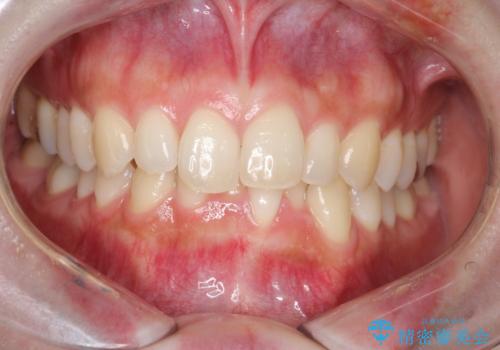

- 患者様は、下顎両側の第1大臼歯(6番)と右上6番の欠損を主訴に来院されました。

通常であればインプラントによる補綴が第一選択となる症例でしたが、患者様ご自身がインプラントを希望されなかったため、矯正治療によって欠損部の閉鎖を図る方針としました。

同時に、親知らず(智歯)の萌出や位置も考慮し、咬合全体のバランスを改善する矯正治療計画を立案しました。

ワイヤー矯正を用いて、欠損部の閉鎖を目的とした後方からの歯の挺出・移動を行いました。

特に、親知らずを活用し、奥歯の噛み合わせを構築することに重点を置きました。

最終的には予定通りインプラントを使用せずに欠損部を閉鎖し、咬合も安定させることができました。